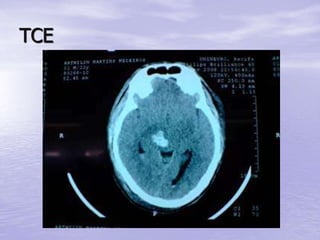

TCE

–Lesão focal - Hemorragias

Cerebrais

– Hemorragias e

– Lacerações Cerebrais

Ferimento por Arma de Fogo

• Mistura de todos os tipo de

lesão, fratura, hemorragia,

hematomas etc...

• Quanto maior o calibre e a

velocidade do projétil, maior

a probabilidade de lesões

graves e a até letais.

• Cobrir a entrada e saída do

projétil com compressa

esterilizada até o tratamento

neurocirúrgico ser

providenciado.